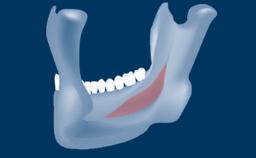

- describe the indications for digital guides in SFE